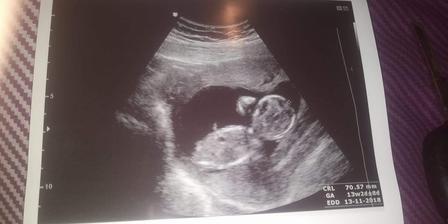

Náš malý uzlíček v mamkinom brušku ( a ako rastieme )

Tie najúžasnejšie mesiace , čo sa môjho života týkajú. Aj ked nie vždy čo sa tehotenských stavov týka najlahšie , ale stojí to za to malé klbko👶👼👨👩👧💝